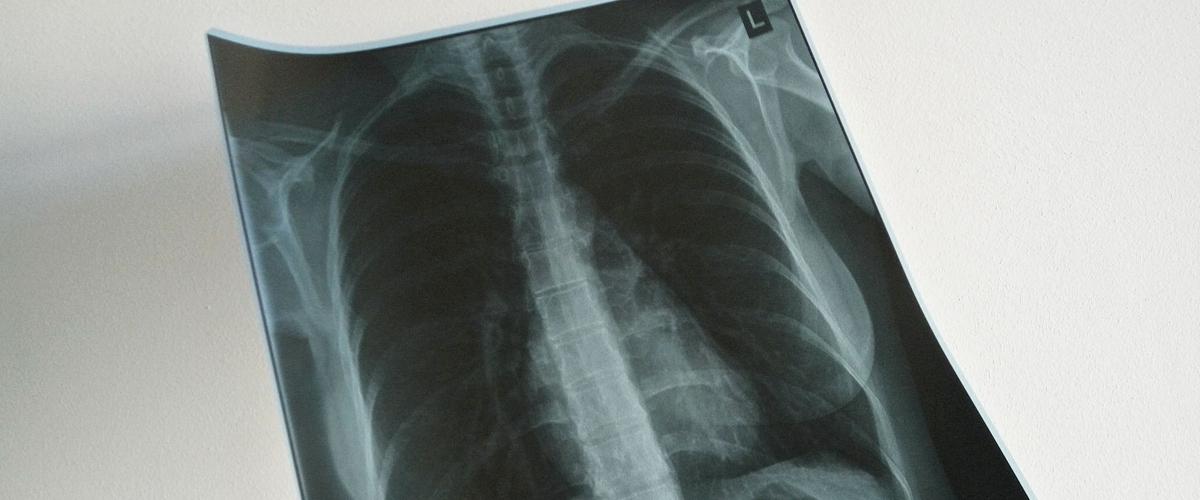

Сканирование с помощью томографа показало, что часть этих изменений связана с повреждением легких и накоплением в них жидкости. На снимках затронутые участки напоминают матовое стекло.